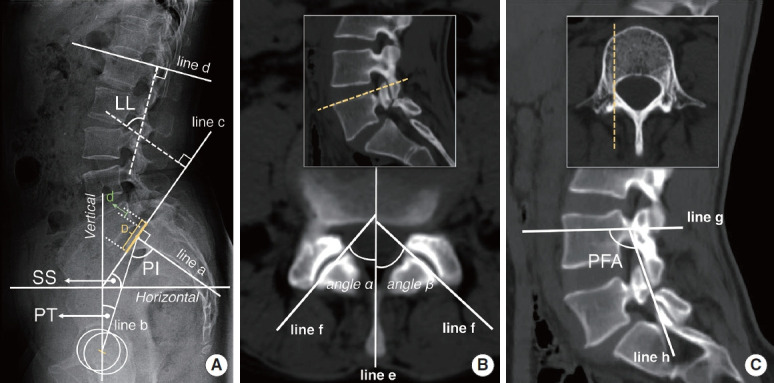

Results: Sacral slope (SS) and lumbar lordosis (LL) were the highest in the IS group, the second highest in the DS group, and the lowest in the NL group. Among the 3 groups, the L4 facet joint angle (FJA) was the largest in the IS group, the second largest in the NL group, and the smallest in the DS group. The L4 pedicle-facet joint angle (PFA) was the largest in the DS group, the second largest in the IS group, and the smallest in the NL group. Pearson correlation analysis showed that within each group, SS and LL were negatively correlated with FJA and positively correlated with PFA.